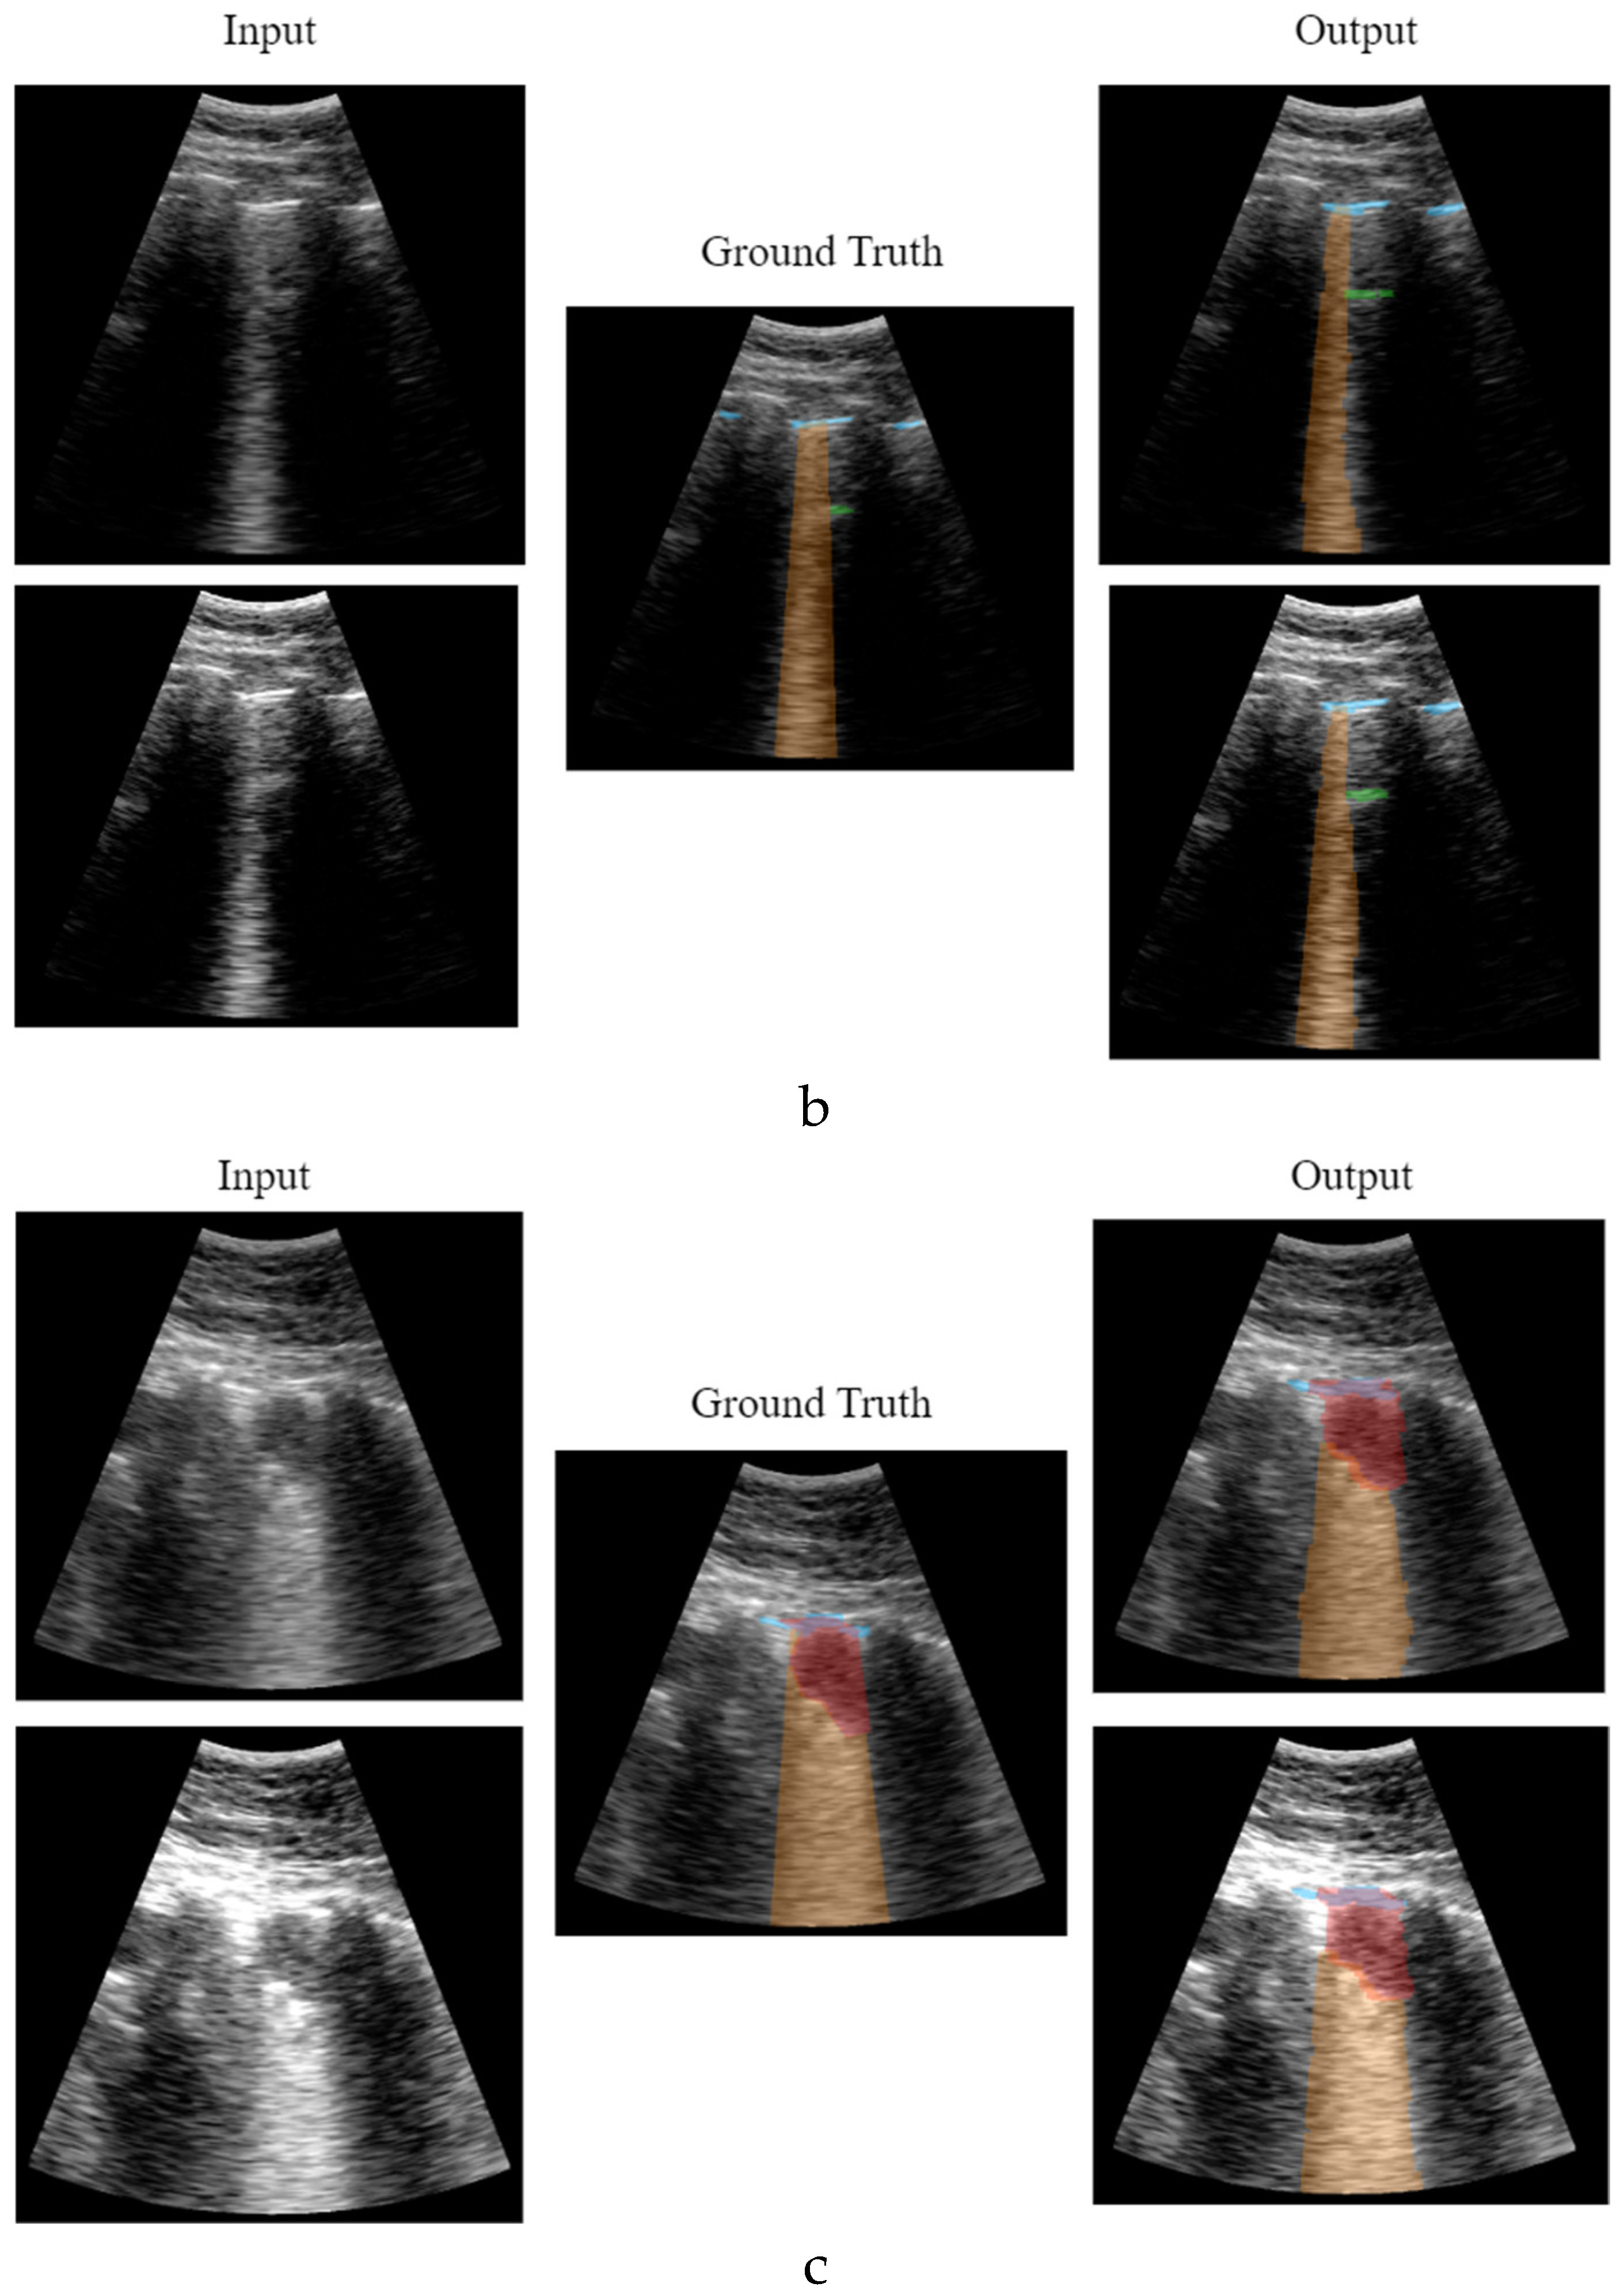

As explained in the validation section, a study was conducted to validate the model's response frame by frame. The results are presented in Table 1, Table 2, Table 3 and Table 4, where the Dice coefficients, Intersection over Union (IoU), F1-score, recall, and precision values are calculated. Figure 11 shows the behaviour of the model applying different thresholds to the network output showing the mean values of the metrics in the test dataset. Given the stability of these results, it makes sense to apply 0.5 as a generic threshold to the network output.

Figure 12 shows different network output examples modifying the saturation of the image at the input of the network, to simulate the gain variation usually applied on an ultrasound scanner. Segmentation and detection of artifacts remains stable, guaranteeing correct operation in spite of signal saturation.

Figure 12. Results comparative with different image gain: a) healthy lung; b) pathological lung; c) grave lung.

Figure 12.a shows the learning and generalization capacity of the trained model. The labelling algorithms of the A-line only considers a single A-line at double the distance between the probe and the pleura; however, the model is able to detect the second and even the third echo in some particular cases, demonstrating the capacity of the model in generalizing and learning the problem. It is worth to mention that this fact negatively affects the validation metrics calculated in Table 2 and Table 4, where the false positive values for A-lines are higher. This is because the second and third occurrences of the A-lines are not labelled in the input dataset, which is a limitation of the labelling algorithm rather than of the model itself.

3.2. Real-Time Implementation Results

As already mentioned, the implemented software is able of processing and displaying in real-time the pleural line, B-lines, consolidations, and A-lines. The algorithm can calculate and obtain the percentage of pleura affected by B-lines, which could be useful to physicians when classifying and determining the severity of a patient’s condition.

The implementation proposed in this study achieves a processing rate of up to 20 predictions and image update per second using an octa-core i5 CPU processor and a NVIDIA GeForce RTX 2060 GPU, which is a medium-range hardware set-up. This figure coincides with the frame-rate given by the ultrasound scanner, so we can state that the solution operates in strict real-time. In terms of computational cost in the different processes, the main process takes about 10ms, which gives a fluid and latency-free feeling during the scan, while the real-time computation process takes about 50ms of which 20-25ms is for model inference on the GPU. It is worth to mention that the final image refresh rate depends on the number of artifacts detected, due to the respective post-processing and painting algorithms which are not yet optimized. Therefore, the effective frame rate obtained was between 17 and 20 FPS,

Regarding prediction capability at the video level, the results given by the model are compared with the opinion of an expert physician. Two different calculations are performed: first, its performance with the test dataset is assessed (Table 5), and second, a specific comparison is made for the set of patients excluded from training (Table 6). With these results it is worth noting that the number of false positives and false negatives are balanced in the case of detection of consolidations and B-lines, which is positive since it is a sign that there is no bias in the training.

It can be observed that the accuracy of the proposed solution at the video level is quite high and it behaves stably even with patients out of training. In the case of the detection of A lines, the results are notably worse than for consolidations and B-Lines, and this because in the labelling process carried out by the physician in [20] labelling the A lines was not mandatory, given that they are indicative of healthy lungs. Therefore, the dataset labelling contains false negatives in those videos where the A-Line is present, but it was not marked by the physician. This is a limitation of this study, but it does not imply that the performance of the solution is nevertheless promising.

Figure 13 shows several examples of the screen of the implemented software in operation explained in Section F.4.